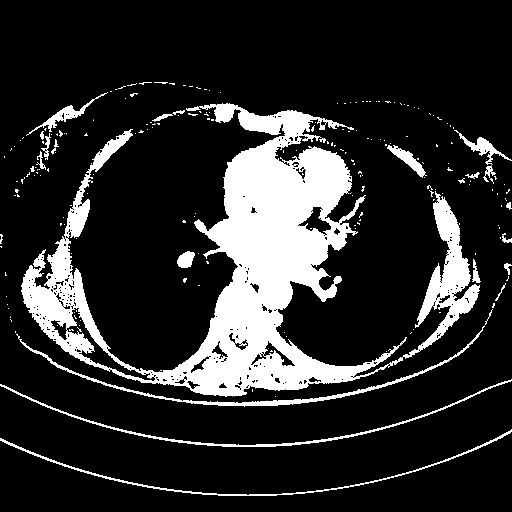

Generated VENOUS CT scan (A→B translation)

Full window (WL 1023.5, WW 4095 β†’ Low βˆ’1024, High +3071)

Actual HU range: [-1024.0, 3071.0]